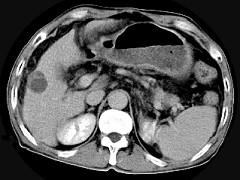

问题 男,63岁,肝区疼痛不适一个月,皮肤巩膜无黄染,AFP高于正常,CT所见如图,最可能的诊断是 ( )

选项 A.肝血管瘤 B.肝转移瘤 C.阿米巴肝脓肿 D.不典型肝癌 E.胆管细胞癌

答案 D